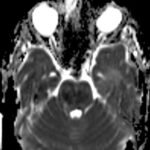

There is a growing body of literature and scientific discovery on pediatric autoimmune encephalitides. This is a heterogenous group of neuroinflammatory conditions leading to often perplexing acute and progressive neurologic and/or neuropsychiatric symptoms. This report demonstrates the evaluation and management of an adolescent with myelin-oligodendrocyte glycoprotein (MOG) antibody-associated fulminant acute disseminated encephalomyelitis (ADEM) in the context of current literature. The featured magnetic resonance imaging uniquely highlights progressive central nervous system lesions detected over the course of the first week of disease.